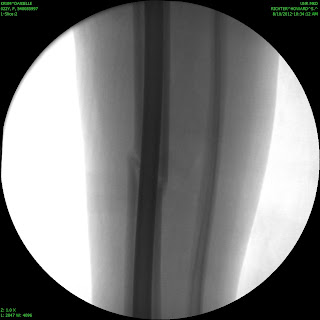

Sorry that I have been MIA for so long! I actually broke my leg on August 9th… I fractured my tibia (the big weight bearing bone in your shin) all the way through. I had the option to be in a full length cast (from my hip to my toes) for 8 weeks, or to have surgery and a rod placed so that I can walk on my leg. I chose to have surgery and now I am just going through recovery. I am working on teaching myself how to walk normal with that leg again. I am happy to be up and moving and not in a cast, but its definitely not a fun process. I have new crafts to put up soon! Some darling candy corns and a pumpkin set for the porch! I will work on getting those posted as soon as I can.

Here are some awesome pictures of my broken leg!